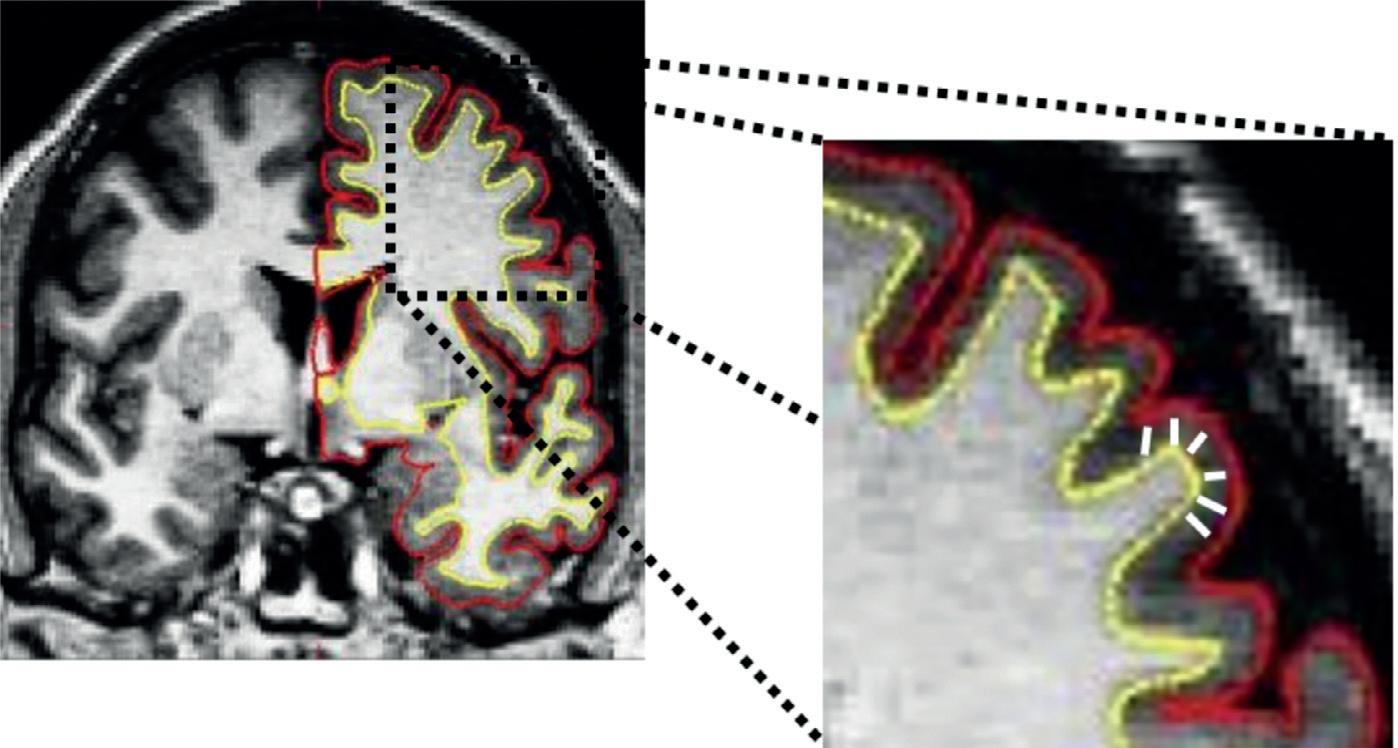

took part in the survey are referred to as ‘respondents’. For more information about the methodology, see bit.ly/3BUgh2a